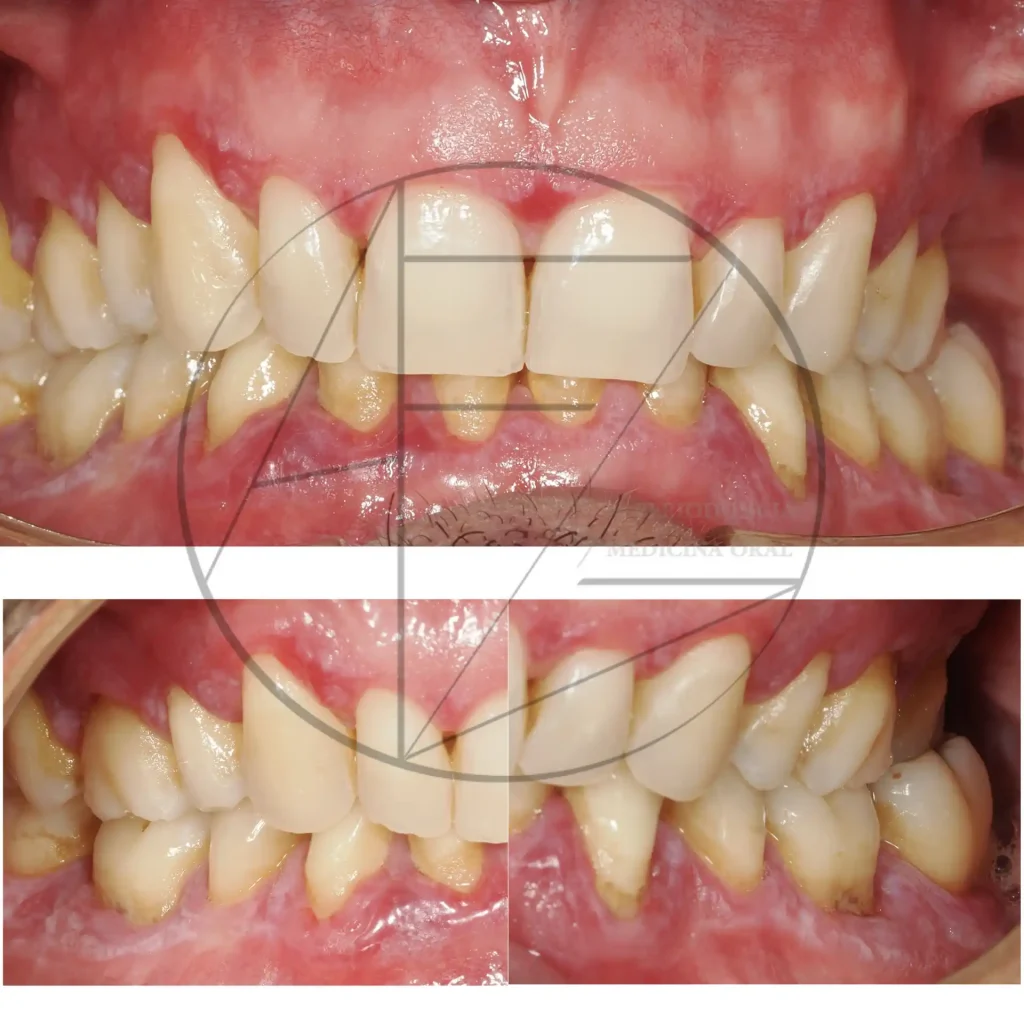

Periodonitis

Periimplantitis